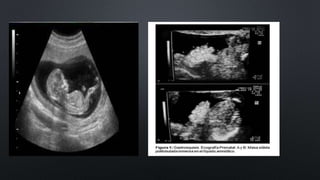

Gastroquisis